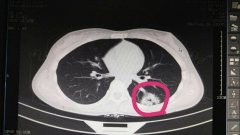

蔡**,女,14歲因反復(fù)頭暈3年余,求診福州及莆田各三級(jí)醫(yī)院,做過(guò)很多輔助檢查,均未確診,于2……